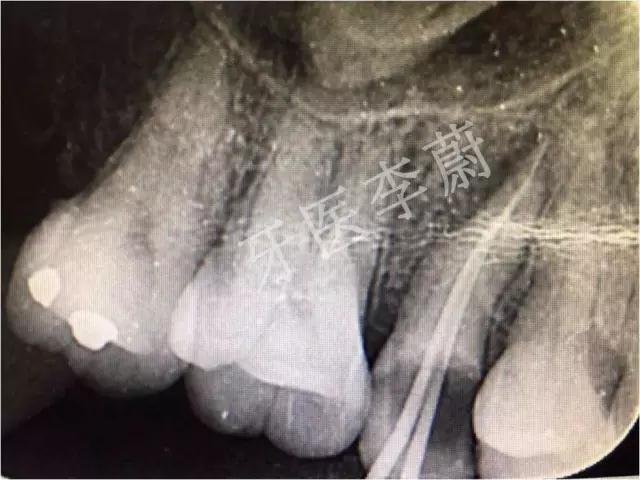

15牙根管充填术后X牙片